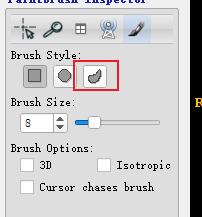

Crosshiar Tool即图像中的十字虚线定位点Zoom/Pan Mode用来缩放图像Polygon Drawing Mode多边形勾选区域,可以设定选定的模式,1)使用Smooth curve2) 使用Polygon多边形PaintBrush Mode用来涂画标注的区域Active Contour Segmentation Mode半自动进行区域的标注Annotation Tool可以标注图像上两点之间的距离,

- 使用画笔工具进行涂画,选择不同的大小进行边界以及内容的填充,选择边界自适应填充可以根据不同的CT值,来填充不同的区域